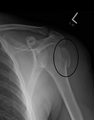

A fracture of the greater tubercle as seen on AP X ray

A fracture of the greater tubercle of the humerus